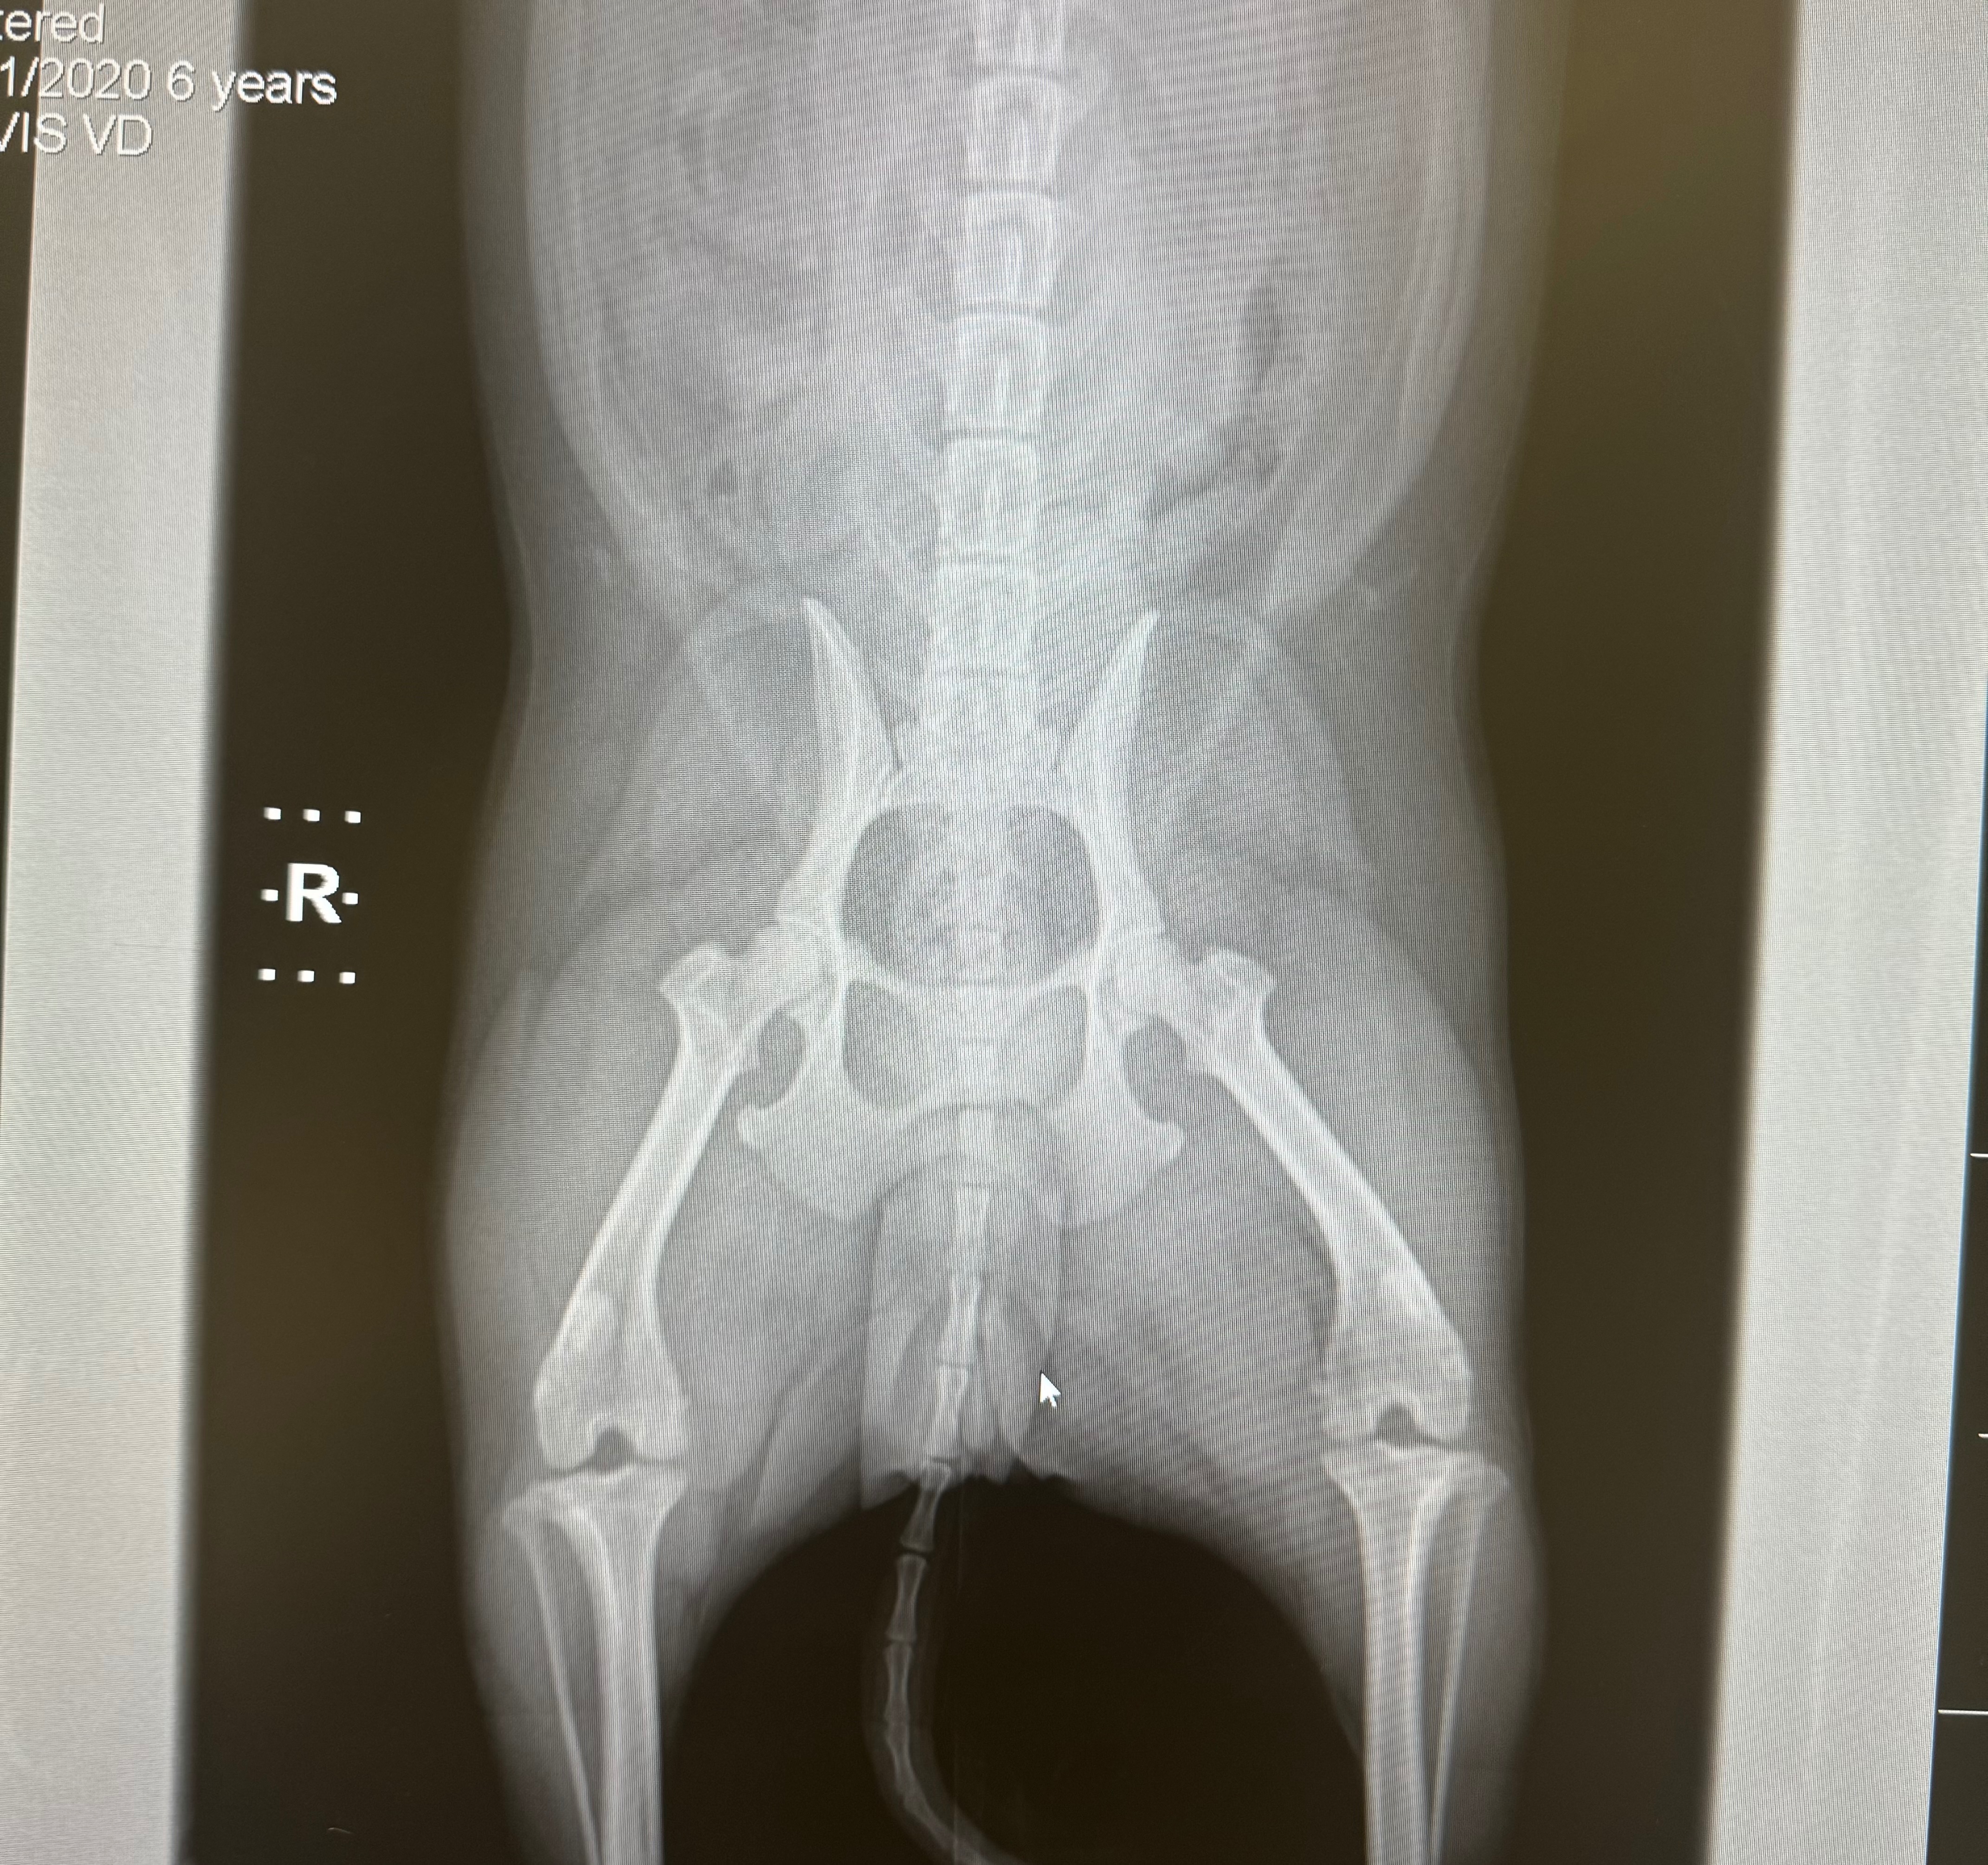

I thought I’d never have to make a post like this, and it pains me to say that Stella is going to need an MPL + TPLO knee leg surgery ASAP.

Unfortunately, a few days ago, my younger siblings took my dog on a walk, and a stranger's off-leash dog charged at her, completely running her over, causing her to tear her ACL and pop her knee out of place. My dog was left crying in the grass, and as my sister went to check on her, the owner took off, and we have not been able to find him since.

Unfortunately, without the owner's information, and both my siblings being underage, I am left with figuring out and managing Stella’s care and rehabilitation while still managing to work as a vet tech. She is only 6 years old and can never sit still, and I’d hate to take that from her, her freedom to move, especially so soon. If I were to leave her untreated, it could possibly develop into a hip issue and much worse, and I don’t want her to suffer any longer than she should.